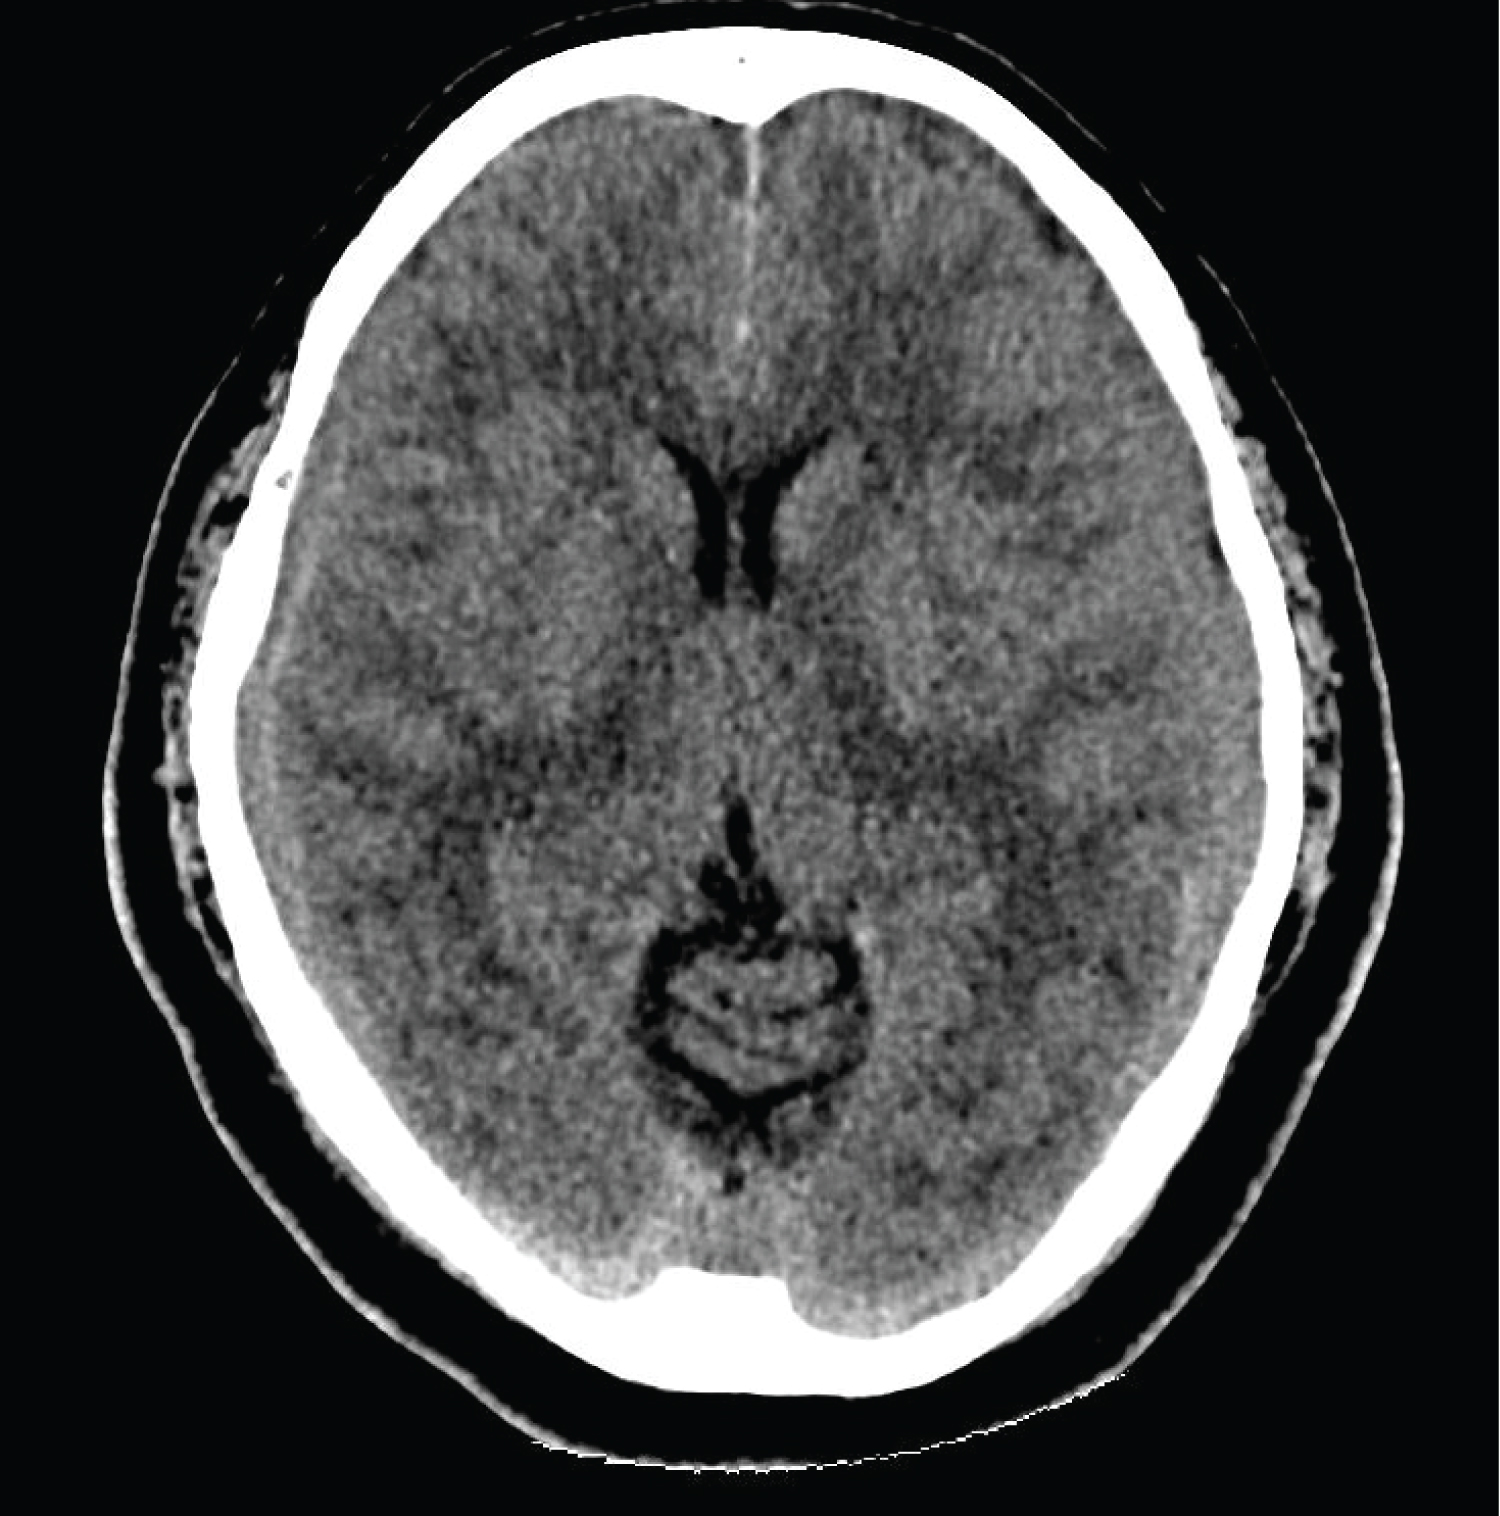

On this second presentation, clinical examination demonstrated diplopia that exacerbated with right gaze and left head tilt, consistent with worsening left trochlear nerve palsy. There were no other neurological deficits. CT-brain revealed bilateral subdural haematomas and mild obliteration of the suprasellar cistern with suggestion of sagging of the brain stem (Figure 1). Magnetic resonance imaging (MRI) of the brain showed bilateral holo hemispheric subdural haematomas (right 0.7 cm, left 1 cm) and sagging of the hypothalamus which raised the suspicion of intracranial hypotension. Diffuse pachymeningeal enhancement was seen (Figure 2). MRI whole spine was done. However, this failed to reveal any dural abnormality or extradural CSF fluid collection that would suggest a high flow CSF leak.

Figure 1: CT-brain: Axial image showing bilateral subdural haematomas. View Figure 1